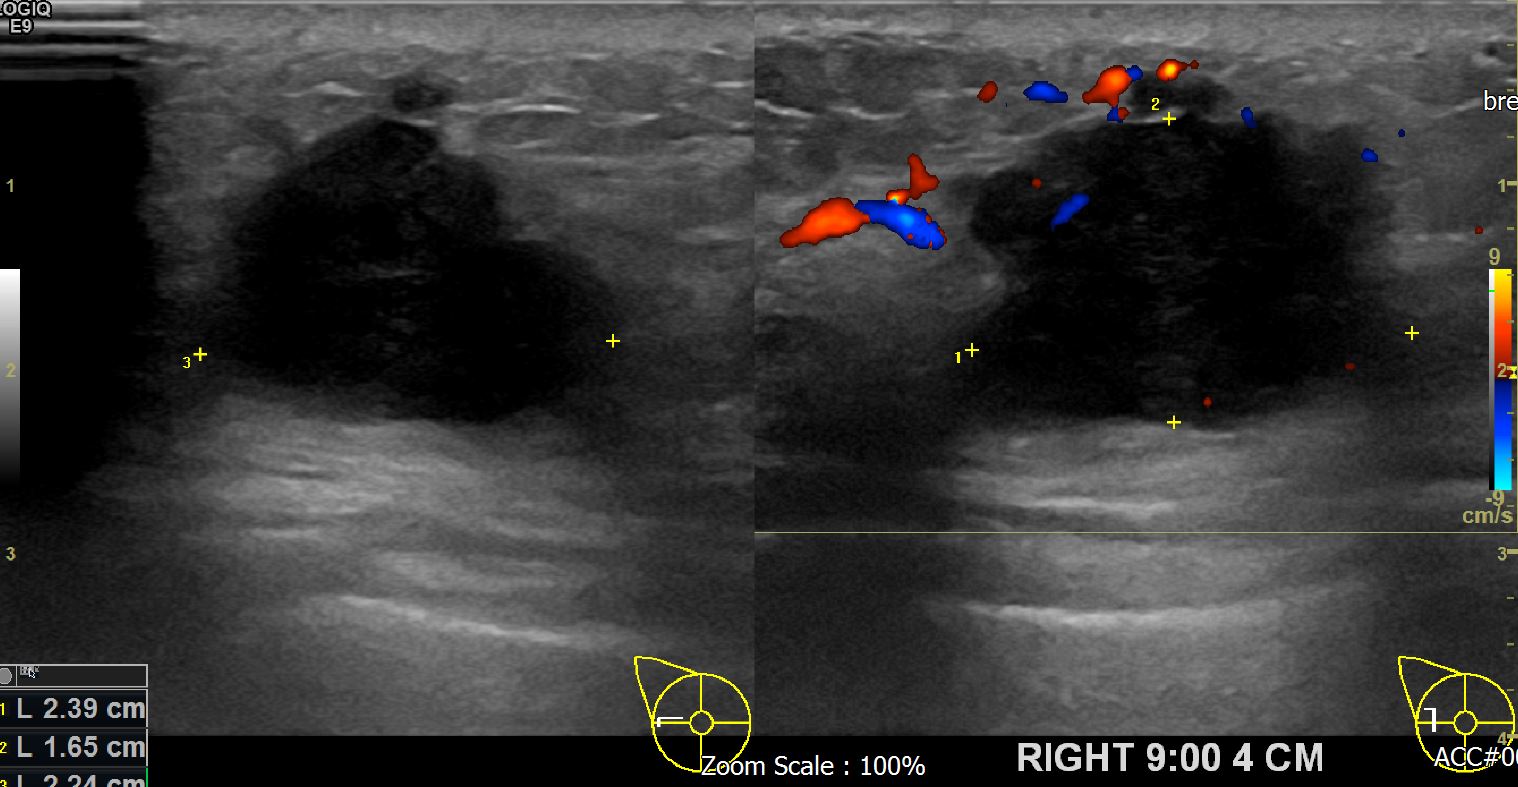

아산유외과 개원후 622번째 유방암진단

상기 환자 외부검사상 이상소견으로 내원하신 50대 여성으로 우측에 의심스러운혹있어 조직검사 시행후 유방암 진단되었습니다.